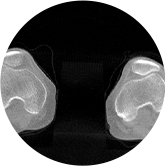

髖關節

FOV 250mm

FOV 350mm